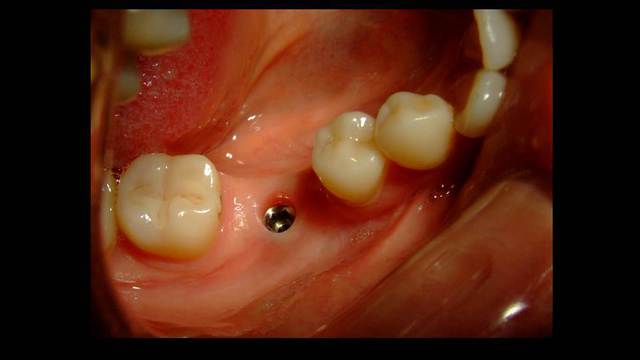

Mais tu aurais attendu 10 jours que la muqueuse se referme et tu pouvais avoir une jolie gencive attachée à déplacer en vestibulaire, ce qui fait défaut ici ...

Ici l'EII (extraction implantation immédiate) n'était pas indiquée à mon avis. Risque d'échec augmenté (suture ouverte) pour aucun bénéfice pour le patient.

Extraction, pose à 45 jours, implant plus large bien centré (meilleur profil d'émergence = hygiène facilitée).